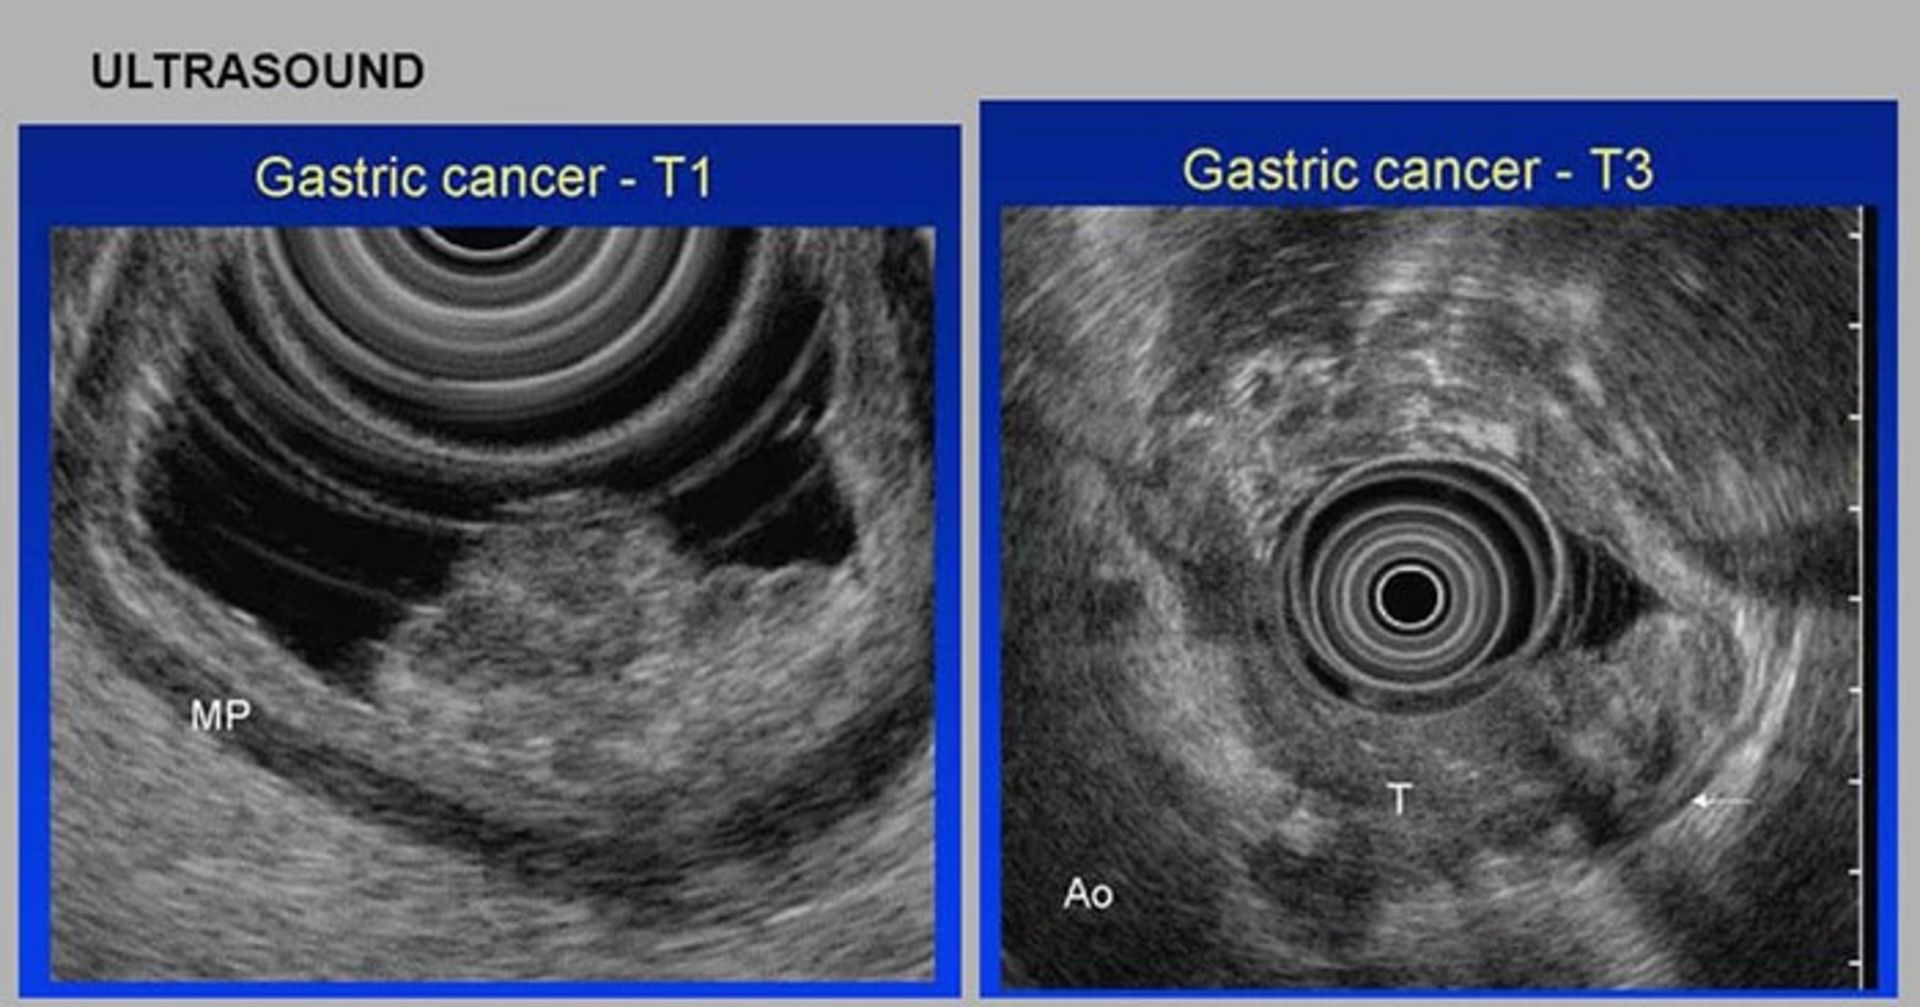

اولتراسوند آندوسکوپی: در روش اولتراسوند از امواج صوتی برای تولید تصاویری از اندامهایی مانند معده استفاده میشود. طی یک اولتراسوند استاندارد، یک ابزار عصامانند که مبدل نامیده میشود، روی پوست قرار داده میشود. این دستگاه امواج صوتی تولید میکند و سپس امواج بازگشتی از اندامهای داخلی را تشخیص میدهد. الگوی این اکوها توسط یک کامپیوتر پردازش میشود و یک تصویر سیاهسفید روی صفحهی نمایش نشان داده میشود. در اولتراسوند آندوسکوپی (EUS)، یک مبدل کوچک در انتهای آندوسکوپ تعبیه میشود. پس از آماده شدن بیمار، آندوسکوپ از گلوی او عبور داده میشود و به معده میرسد. با این کار مبدل میتواند روی دیوارهی معده، جایی که سرطان میتواند وجود داشته باشد، قرار گیرد. پزشکان میتوانند لایههای معده و نیز گرههای لنفاوی و سایر ساختارهای نزدیک معده را مورد بررسی قرار دهند. کیفیت این تصویر بهعلت فاصلهی کوتاهتری که امواج صوتی طی میکنند، از تصویر حاصل از یک اولتراسوند استاندارد بهتر است. مزیت اصلی روش EUS در ارتباط با مشاهدهی میزان انتشار سرطان در دیوارهی معده، بافتها و گرههای لنفاوی مجاور است. این روش همچنین میتواند برای هدایت سوزن بیوپسی (نمونهبرداری) استفاده شود.